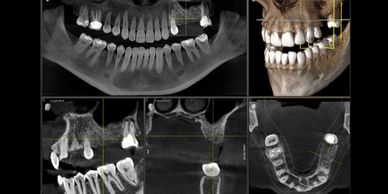

We have the latest in 3D low dose x-ray technology (Cone Beam Computed Tomography) that allows us to visualize areas like never before. This provides increased diagnostic and treatment planning capabilities.